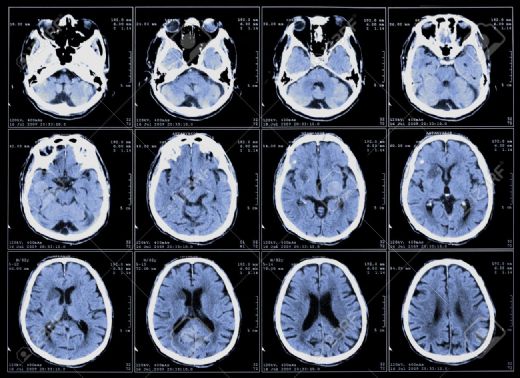

Beyin Tomografisi

Beyin tomografisi, beynin yapısal özelliklerini ve olası patolojik durumları değerlendirmek amacıyla kullanılan önemli bir görüntüleme yöntemidir. Bilgisayarlı tomografi (BT) ve manyetik rezonans görüntüleme (MRG) teknikleriyle gerçekleştirilir. Klinik durumların tanısı ve tedavi planlamasında kritik rol oynar.

Görüntülerin Yorumlanması Elde edilen beyin tomografi görüntüleri, uzman radyologlar tarafından incelenerek yorumlanır. Görüntülerde anormallikler, lezyonlar veya diğer patolojik durumlar gözlemlenebilir. Radyologların, görüntüler üzerinde yapacağı değerlendirmeler, hastanın klinik durumu ve belirtileriyle birlikte ele alınarak tanı ve tedavi sürecine yön vermektedir. Sonuç Beyin tomografisi, nörolojik hastalıkların tanısını koymak ve tedavi planlaması için vazgeçilmez bir araçtır. Bu görüntüleme yöntemi, gelişen teknoloji ile birlikte daha hassas ve detaylı sonuçlar sunmakta, böylece hastaların sağlık durumlarını daha iyi yönetmeye yardımcı olmaktadır. Ekstra Bilgiler Beyin tomografisi ile ilgili birkaç ek bilgi: